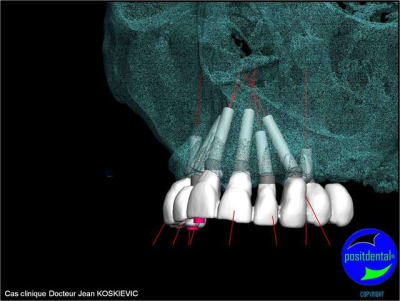

Chirurgie passée

et la projet 10 implants maxillaire sup

et là béotien ?

10 en haut